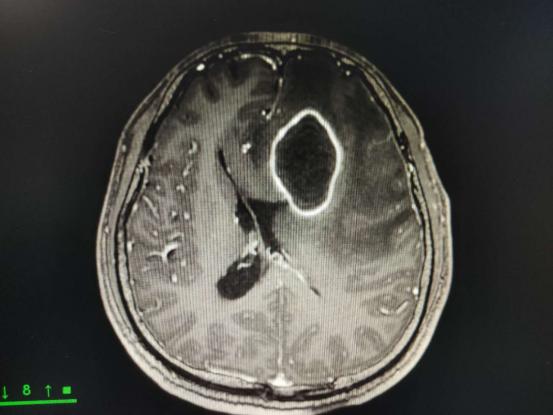

左额叶深部中线旁可见体积较大的脑脓肿,并周围大片脑水肿,颅内压明显增高,占位效应显著